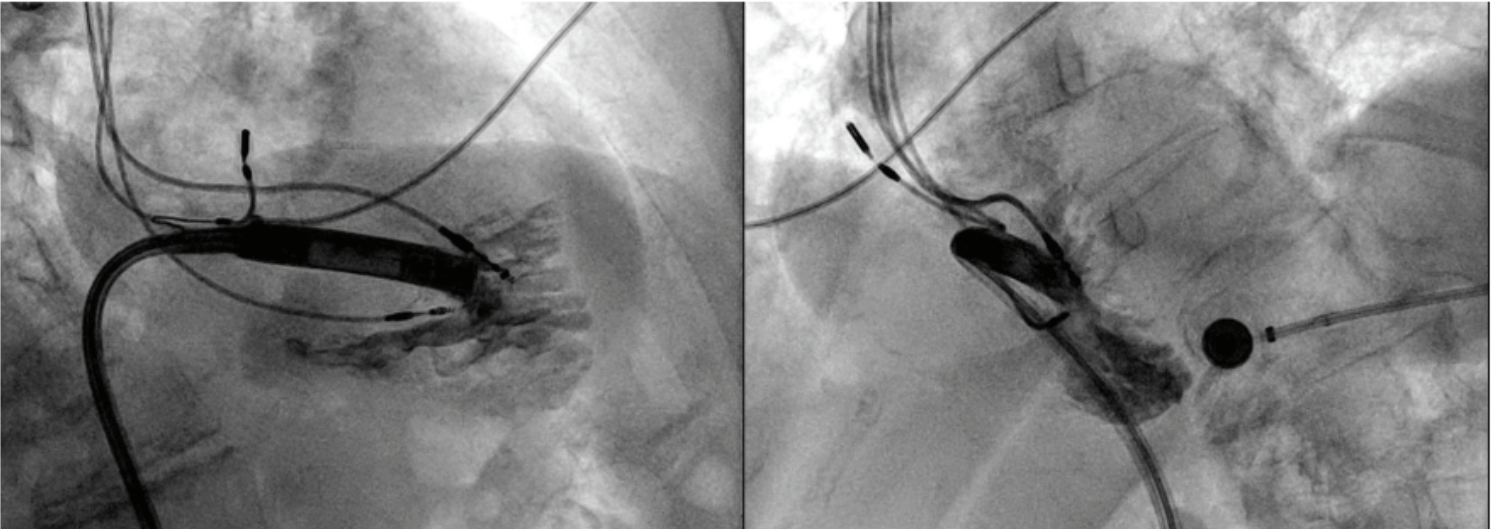

The main challenge during the time of implantation was to “thread the needle” and place the leadless pacemaker between the 2 transvenous ventricular leads in situ such that the implantation site was safely on the septum without lead-leadless pacemaker interference.

The AVEIR catheter was advanced through the 25 French introducer sheath to the right atrium, and gently navigated through the tricuspid valve

and into the RV (Figure 2). Contrast-enhanced cine images in left and right anterior oblique projections confirmed appropriate low septal positioning (Figure 3). Passive mapping demonstrated excellent injury current.